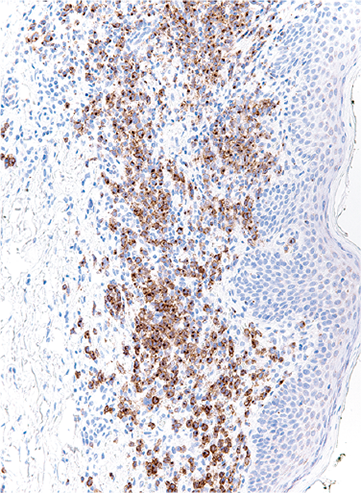

A skin section from a patient with Sézary syndrome was stained for CCR4, highlighting expression of CCR4 by malignant skin-infiltrating lymphocytes. On rebiopsy at progression during treatment of the patient with mogamulizumab, CCR4 expression was no longer detectable. See the article by Beygi et al on page 3732.

Resistance to mogamulizumab is associated with loss of CCR4 in cutaneous T-cell lymphoma

Expression of the chemokine receptor CCR4 is upregulated in all stages of cutaneous T-cell lymphomas (CTCLs). Mogamulizumab, a humanized anti-CCR4 monoclonal antibody that induces antibody-dependent, cell-mediated cytotoxicity, is FDA approved for treatment of relapsed CTCL, yet primary resistance and early relapse are common. Beygi and colleagues reveal that in samples from 17 patients with CTCL failing mogamulizumab therapy, the majority lost CCR4 expression, variously due to gene disruption, loss-of-function mutations, or epigenetic mechanisms.